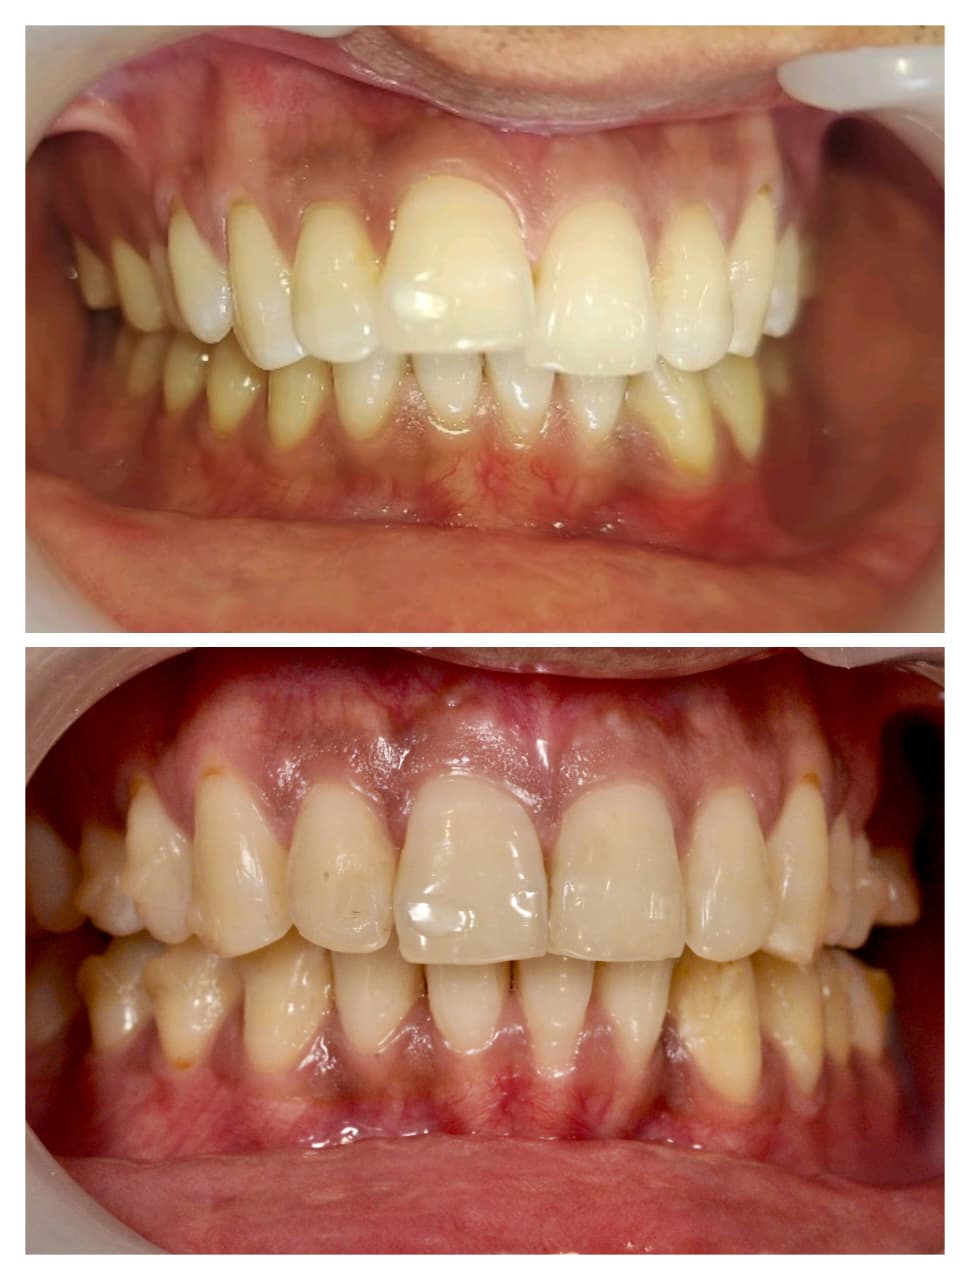

Smile Gallery